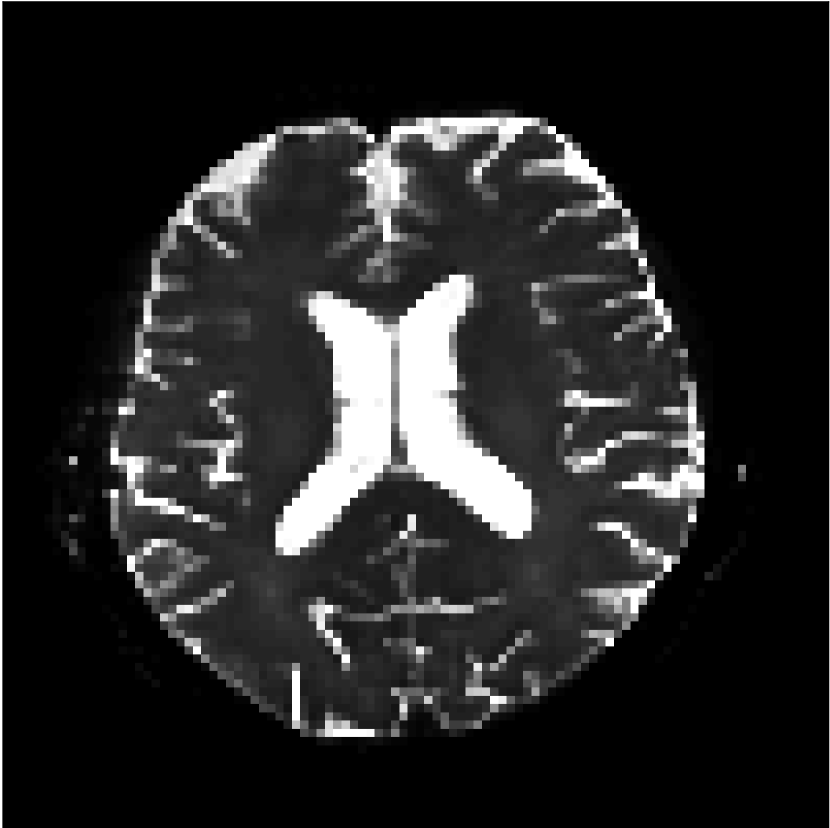

Figure 9 shows parameter maps for the different methods without partial Fourier (No PF) and with 5/8ths partial Fourier (5/8 PF). Mean diffusivities calculated from the raw DWI data (Raw) show notable noise and Gibbs ringing artifacts, while this is substantially removed with the state-of-the-art (SoA) method. However, the state-of-the-art method begins to lose its ability to compensate for the Gibbs ringing and resolution loss when partial Fourier is utilized in the acquisition. The effects of partial Fourier increases are primarily evident in the enlargement of the lateral ventricles and the presence of black lines in the vicinity of the lateral ventricles. The MCNN model is able to compensate somewhat for the ringing effects, but begins to introduce substantial artifacts at the 5/8ths partial Fourier factor, whereas the CCNN model continues to give high-quality mean parameter maps across all PF factors.

Raw

SoA

MCNN

Standard PF

CCNN

MK

Figure 9: Parameter maps from various methods (with CSF masks for FA and MK). At the top are shown the b=0𝑏0b=0 images from Raw, state-of-the-art (SoA), MCNN, standard partial Fourier, and CCNN methods. Rows 2 and 3 show results for mean diffusivity, rows 4 and 5 show results for fractional anisotropy, and rows 6 and 7 show results for mean kurtosis. The SoA method and both deep learning methods perform well without partial Fourier acceleration; however, at the 5/8ths partial Fourier factor, substantial artifacts are present for all methods other than the CCNN method.

Similar trends are observed in the other diffusion parameter maps.